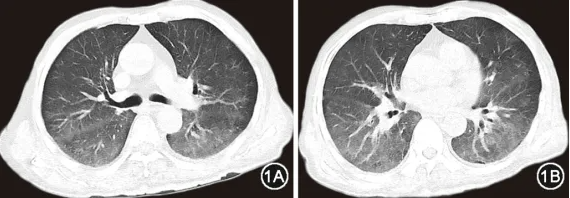

入院体检:心率106 次/min,血压157/114 mmHg(1 mmHg=0.133 kPa),外周指脉氧饱和度94%(文丘里面罩氧浓度31%支持),双肺呼吸音粗,心律齐,腹软,双下肢轻度可凹性水肿;时间定向力、计算能力差,双上肢肌力5级,下肢肌力3+级。入院后完善辅助检查:血气分析(吸入氧浓度37%):pH值为7.45,PaCO2为20 mmHg,PaO2为66 mmHg,cHCO3-为18.1 mmol/L,cLac为6.1 mmol/L;LDH为2 573 U/L;铁蛋白 1 641 ng/ml;白细胞介素(interleukin,IL)-10为134.0 ng/L。自身抗体谱:抗核抗体斑点型阳性,滴度1˸320;抗中性粒细胞胞质抗体(antineutrophil cytoplasmic antibodies,ANCA)核周型阳性,滴度1∶20。胸部CT示双肺弥漫性磨玻璃样病变,呈重力分布(图1)。

图1 患者2023年9月6日胸部CT检查可见双肺弥漫性磨玻璃影,呈向心性、重力依赖性,沿支气管、血管束分布,以双下肺为著,胸膜下较少累及

本例患者为老年男性,临床主要表现为快速进展的呼吸困难,伴发热、消瘦等全身炎症状态。病初糖皮质激素治疗有效,但减量后病情反复,后期出现神经系统和血液系统受累。实验室检查提示血清LDH、IL-10显著升高,多次筛查外周血、下呼吸道病原学均无感染性疾病相关证据,虽存在ANCA低滴度阳性,但无咯血、血红蛋白明显下降等显微镜下多血管炎典型弥漫性肺泡出血表现;而影像学检查以肺内病变较为突出,胸部CT表现为双肺沿重力分布的弥漫性磨玻璃影(ground glass opacity,GGO),且PET/CT提示代谢性摄取增高,同时超声提示脾大。因此需高度警惕弥漫浸润的血液系统肿瘤,经积极寻找病理证据,最终通过TBLB小标本明确诊断。

IVLBCL患者肺受累主要表现为发热、咳嗽和劳力性呼吸困难等非特异性症状[10, 11]。实验室检查常见血清IL-10及LDH显著升高,其水平可能是IVLBCL早期诊断和疗效监测的有效生物标志物[12, 13, 14, 15]。由于大量淋巴瘤细胞聚集在毛细血管内,IVLBCL肺受累典型的胸部CT与其他肺淋巴瘤不同,常表现为双侧弥漫性GGO,其次也可表现为弥漫性分布的小结节影、实变影和小叶间隔增厚等[16, 17, 18],甚至可能无明显异常[19],而非实变和肿块。此外,18F-FDG PET-CT对肺IVLBCL的诊断具有较高提示意义[20, 21, 22],特别是在存在呼吸系统症状但胸部CT未见异常的患者中[21,23],主要表现为双肺均匀弥漫性的代谢摄取增高。